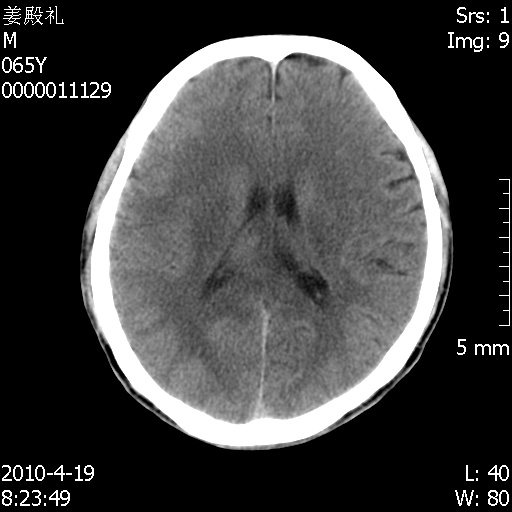

老年男性,突发左下肢无力1天,其余有价值的检查都没有。平扫ct值大约60hu,增强后ct值没什么改变,请大家讨论一下这个病例是什么?说明诊断理由。

左小脑、右大脑顶叶多发圆形高密度病灶,其周环状低密度影。考虑多发脑出血。隔期观察。

今天上班后发现病人前天复查(4月18日发病,19日初诊,22日复查),三个病灶均明显增大,边缘仍旧清楚,水肿加重,右侧脑室基本闭塞。

基于这样的表现,不知大家有什么看法?(临床其他检查我还没有追踪)

我想:如果是肿瘤出血的话,一般不会导致体积明显改变,水肿又进一步加重;如果是出血灶,那么现在应该正好是水肿加重的时候,还是比较符合,但是为什么边缘又是这样的特点?